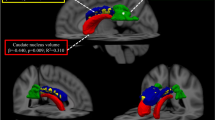

Our healthy control group was highly comparable to our patient groups with regard to age and sex (n = 54, age 39 ± 5.3 years, 39 females; all p values of group comparisons with CP and CI patients, > 0.1). As expected, almost all brain volumes were significantly lower in both patient groups than in the control group. Therefore, we only report the results of the comparisons between patient groups with MS (i.e., CP vs. CI). CI and CP patients did not differ significantly in age, sex and disease duration (Table 1). The latter (CI 5.4 ± 5.6 years) reflected an early disease stage. Compared to CP patients, CI patients showed higher disability as measured by EDSS (3.0 ± 1.7 vs. 1.6 ± 1.1, p < 0.001). As expected, performance in the cognitive screening test MuSIC was much lower in the 28 CI patients in which this test battery was available (20.4 ± 5.5 vs. CP MS patients: 26.7 ± 2.9, p < 0.001). CI patients showed higher WML volume (lgWML 1.14 ± 0.68 vs. 0.50 ± 0.57; corresponding to WML 32.1 ± 34.8 vs. 5.6 ± 9.1 ml) and lower GM volumes (all p values < 0.05 after correction for multiple testing, i.e., for the 12 volumetric parameters). Of note, effect sizes were largest for lgWML and thalamic volume (standardized ß value 0.25 and − 0.25). Less pronounced, we also observed highly significant atrophy of the corpus callosum. Within the patients, all pairs of structural brain parameters were significantly correlated (Fig. 2). Among the parameters with the strongest association to CI, thalamic volume and WML showed the strongest correlation (r = − 0.67, p < 0.001).

Voxel-wise analyses of GM yielded a wide-spread GM decrease in CI compared to CP most pronounced in deep GM. Adjusting for EDSS weakened but did not fundamentally change the result (Fig. 3a, b). Regional analyses of cortical thickness revealed wide-spread cortical thinning in the CI group which was only slightly weakened after adjusting for EDSS (Fig. 4a, b). Aiming at parameters exerting an independent effect on CI, we repeated the voxel-wise and surface-based analyses after inclusion of image-based covariates. In the voxel-wise analyses, thalamic atrophy remained significant after inclusion of cortical atrophy (Fig. 3c) but almost disappeared after inclusion of WML volume (Fig. 3d). Reduced cortical thickness lost significance primarily in the occipital and parietal cortex after inclusion of either thalamic volume or WML, whilst large areas of reduced cortical thickness in frontal and anterior temporal areas remained significant (Fig. 4c, d). To better visualize areas with most pronounced cortical thinning, we lowered the statistical threshold to a p value of < 0.05 family-wise error corrected at the voxel level revealing eight areas: bilateral parahippocampal gyrus (1 and 2), left superior frontal gyrus (3), rostral middle frontal gyrus (4), left middle superior temporal gyrus including transverse temporal gyrus (5), right precentral gyrus (6), right middle temporal gyrus (7), and right supramarginal gyrus (8).

Group comparison of grey matter images. Group comparison of grey matter images between cognitively impaired and cognitively preserved patients with multiple sclerosis after adjusting for different sets of covariates. a Significant grey matter loss in cognitively impaired compared to cognitively preserved patients is depicted adjusting for age, sex, and TIV; b after additionally adjusting for disability; c after additionally adjusting for cerebral cortex; d and after additionally adjusting for white matter lesion volume. Slices are projected onto the Montreal Neurological Institute (MNI) template. Coordinates are indicated for coronal (y), sagittal (x), and axial slices (z). Statistical parametric maps are thresholded at p < 0.05 corrected (threshold-free cluster enhancement). Effects are scaled from dark red to light yellow with the latter indicating more grey matter loss. EDSS Expanded Disability Status Scale, lgWML decadic logarithm of white matter lesion volume, TIV total intracranial volume

Here, we focused on the volumes showing the largest effects of CI, namely WML and thalamic volume. Both volumes were strongly correlated in both CP and CI patients (r = − 0.560 and r = − 0.808, respectively; both p < 0.001). Including the main effects of thalamic volume and WML volume in one binary logistic regression model with the response variable CI/CP (reference variable CI), only WML showed a significant contribution to CI. Including both main effects and their interaction in another model resulted in a higher pseudo-R2 value (suggesting a better model fit) and significant effects of WML volume and its interaction with thalamic volume (Table 2, upper part). Both models remained significant as described after the inclusion of overall disability estimated by EDSS (Table 2, lower part).

Comparing CI to CP patients, differences of three parameters stood out—all well in accordance with the literature: overall disability (i.e., EDSS) [12], WML volume, and thalamic atrophy [4,5,6,7,8,9,10,11]. In addition, voxel-wise analyses confirmed that thalamic atrophy is the most striking difference between CI and CP patients within brain GM, whilst none of the areas of CI-related cortical thinning showed an effect size in this order of magnitude. Although associations of both WML load and thalamic atrophy with CI in MS had been demonstrated before by further evidence [29, 36,37,38,39,40], we were impressed by the robustness of these effects compared to the remaining results. In addition, both parameters were strongly correlated, which had been reported before [27, 41, 42] although not consistently [43]. Against this background, we felt that further analyses focusing on these two parameters were justified. In a common model, only WML volume independently explained the occurrence of CI. Of note, the inclusion of the interaction term of WML volume and thalamic atrophy led to a better overall model fit indicating significant contributions of WML volume and its interaction with thalamic volume. In other words, thalamic atrophy seems to be less problematic than WML, whilst co-occurrence of the two is detrimental. In our opinion, the idea that thalamic atrophy is in part driven by WML through axonal transection of connecting fibers best explains our results [27, 42, 44]. Such an effect of WML on thalamic atrophy is likely to depend on overall volume, eloquence of location, and destructive power (i.e., the extent of axonal transection in a given WML volume). These three are also very likely to increase the occurrence of CI in MS. Hence, we speculate that, in our statistical model, the main effect of WML volume reflects the spatial extent of WML load, whilst the interaction of thalamic and WML volume reflects the destructiveness of WML and their eloquence of location. In contrast, we were unable to demonstrate an independent main effect of thalamic volume in our cohort of patients, who were primarily in the early stages of MS. Yet direct thalamic damage through MS-related pathology exists [45] and may become prominent in later stages.